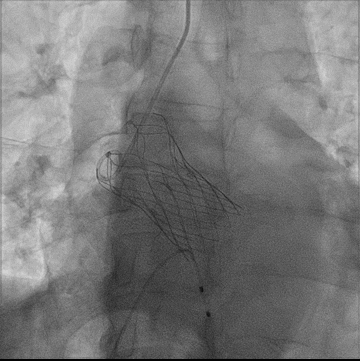

主动脉根部造影

瓣膜定位

瓣膜完全释放形态良好,无瓣周漏